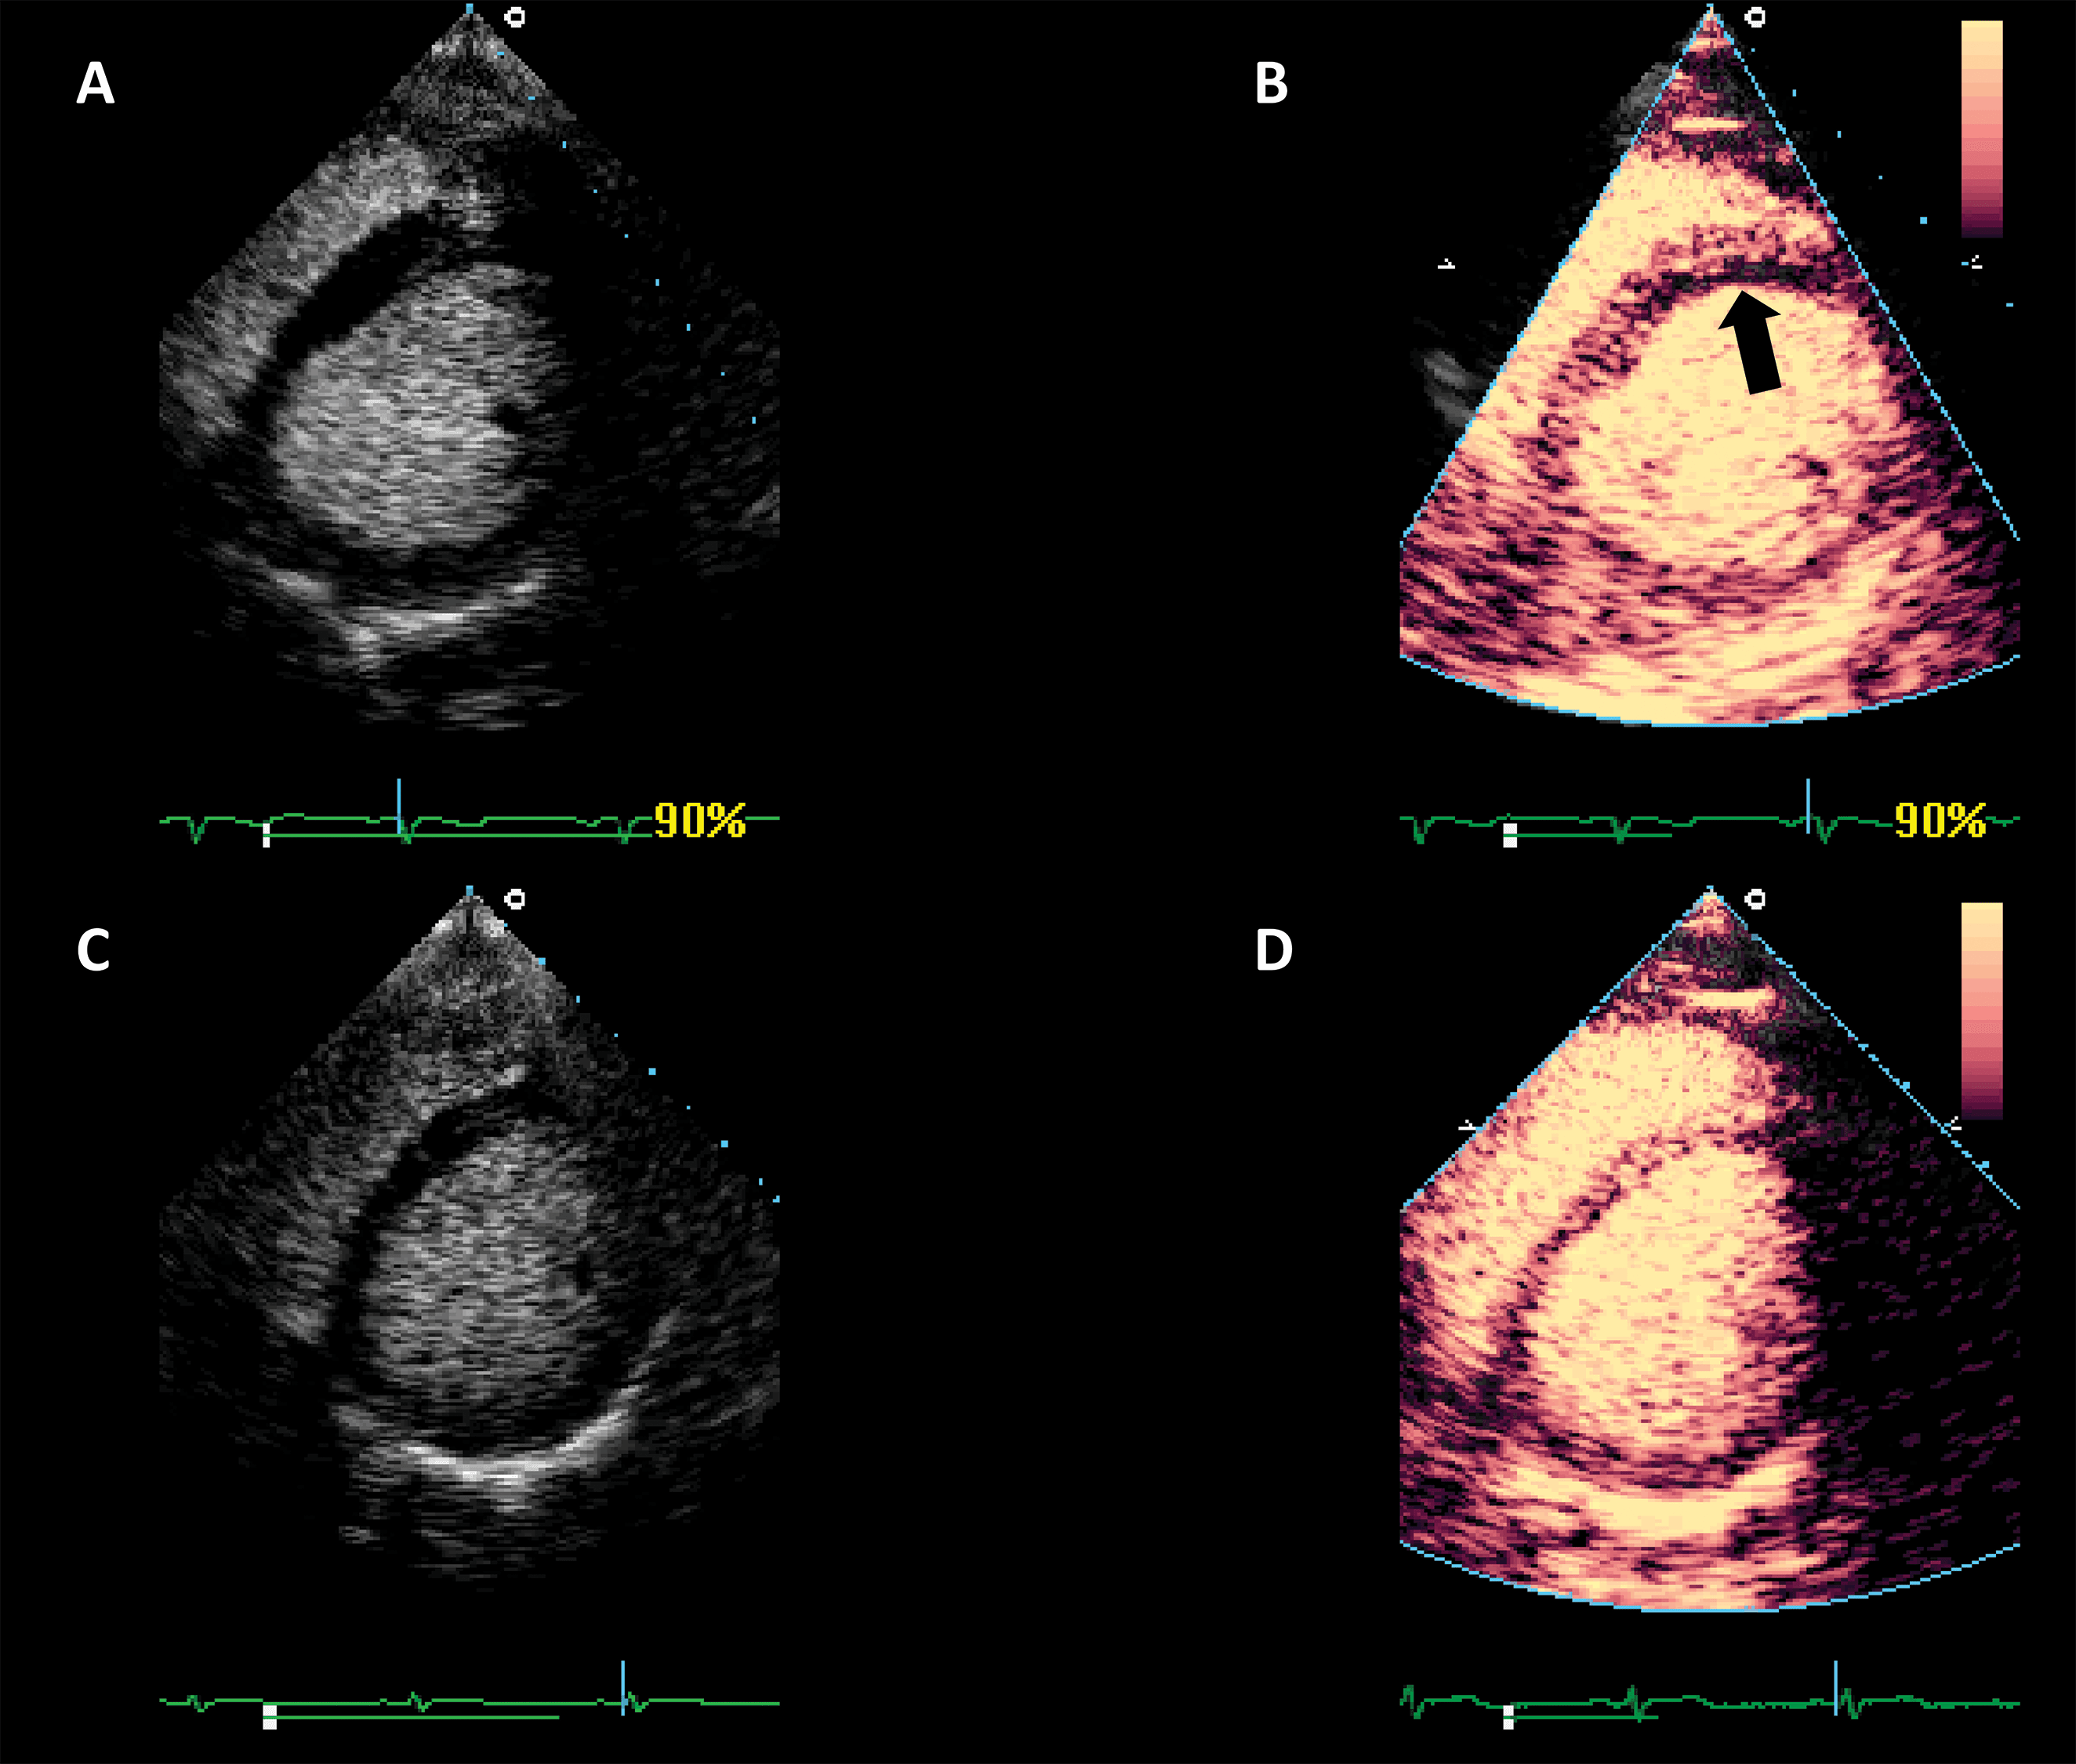

Another application of LVO is morphological diagnosis, particularly in disease states which manifest in the artefact-prone LV apex. Beside possible foreshortening, the LV apex is prone to clutter and reverberation artefacts, while also having a weaker potential to generate harmonics because of its position in the near-field in apical views [28]. As such, apical forms of hypertrophic cardiomyopathy [29, 30], eosinophilic cardiomyopathy [31] and non-compaction cardiomyopathy [32] may escape detection with unenhanced ultrasound.

Numerous case reports and case series document the use of UEA in these instances [29, 30, 31, 32, 33]. Studies have also been performed demonstrating the added value of contrast-enhanced ultrasound in hypertrophic cardiomyopathy [34] (Fig. 4, Video 4).

Fig. 4.Hypertrophic cardiomyopathy patient with very poor image in apical 4-chambers view. (A,B) Native images, end-diastole (A) and end-systole (B). The endocardium of the lateral wall is not visible, and the apex cannot be seen. (C,D) Contrast-enhanced images, in the same moments in the cardiac cycle. The LV contour is clearly delineated, during systole there is complete cavity obliteration, with an apical aneurysm (arrow). Source: personal collection.